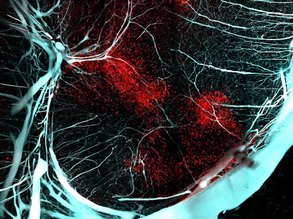

Vessel Makers